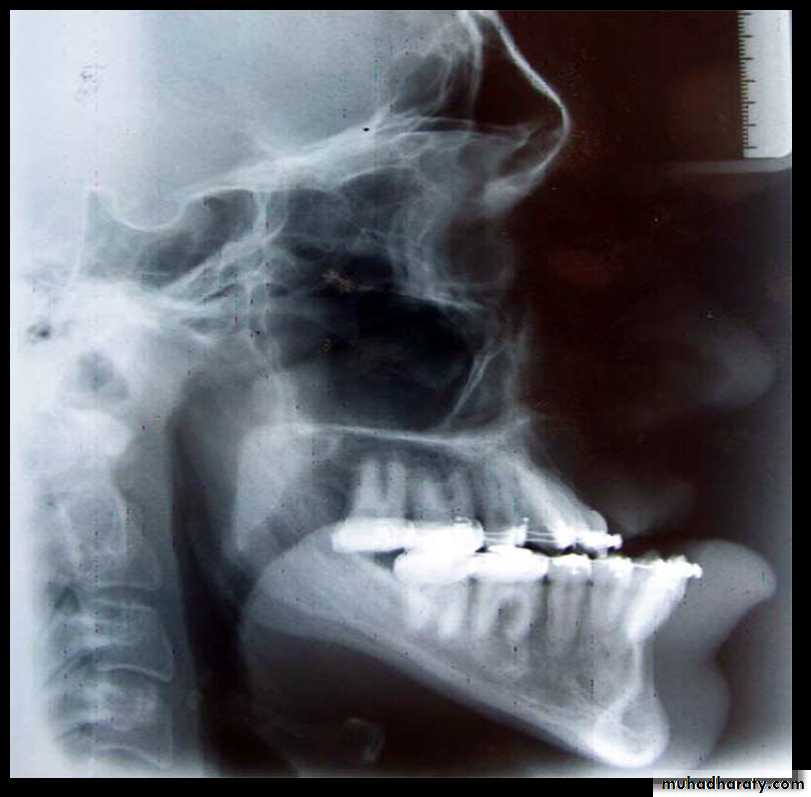

• Cephalometric x-rays provide for standardized skull and/or facial views that allow for comparison over time to assess growth in an individual and for comparison of that individual against standardized population norms. Skeletal views can be obtained in lateral and frontal views.

Lateral cephalometric x-ray also allows the dentition to be related to each other, and each can be related to its own skeletal base, the maxilla, and the mandible.

Periapical films are obtained to determine if sufficient space exists for interdental osteotomies.

Additional radiographs include the following

• Three-dimensional computerized tomography (3DCT) is increasingly being used for surgical evaluation and planning .Dental cast